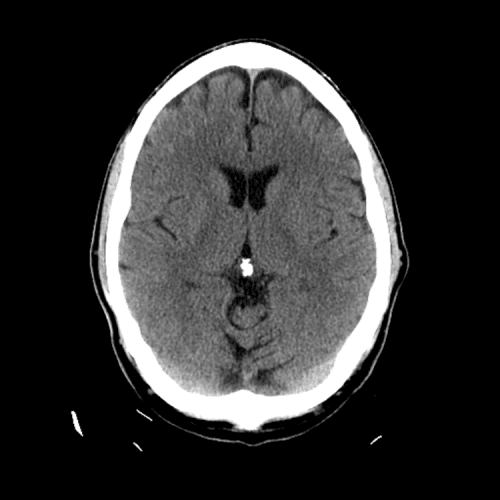

Non-traumatic Head CT Cases

Classic Cases

Includes classic examples of cases commonly seen on call.